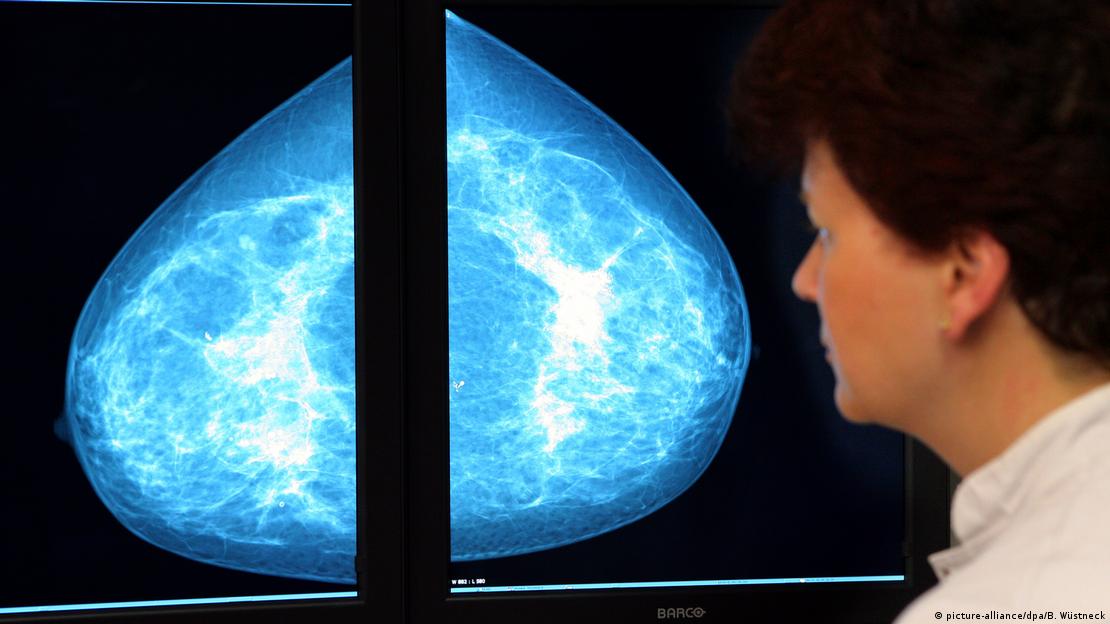

Kuhl, bunun nedenini mamografinin birçok tümörü ya hiç ya da çok geç fark edebilmesiyle açıklıyor. Özellikle hızlı büyüyen ve daha saldırgan olan tümörler mamografide çoğu zaman görünmüyor. Bu tür tümörler, kadınlarda en sık ölüme yol açanlar arasında.

Bugün birçok ülkede 50 ila 75 yaş arasındaki kadınlara iki yılda bir mamografi taraması öneriliyor. Ancak Kuhl, herkesin riskinin aynı olmadığını vurguluyor. Meme dokusunun yoğunluğu hem kansere yakalanma ihtimalini hem de mamografinin bir tümörü yakalama şansını etkiliyor. Doku yoğunluğu arttıkça hem hastalık riski artıyor hem de mamografinin bir tümörü fark etme olasılığı düşüyor.

Klasik yöntemlerle çekilen bir mamagrofide bazı risklerin teşhisi mümkün olmuyor

Kuhl, birçok kadının bu durumu bilmediğini belirtiyor. ABD'de kadınlar, meme dokularının ne kadar yoğun olduğu ve bunun taramayı zorlaştırdığı konusunda yıllardır bilgilendiriliyor. Tıpta "masking risk" olarak adlandırılan bu durum, yoğun dokunun tümörü gizleme ihtimaline işaret ediyor.